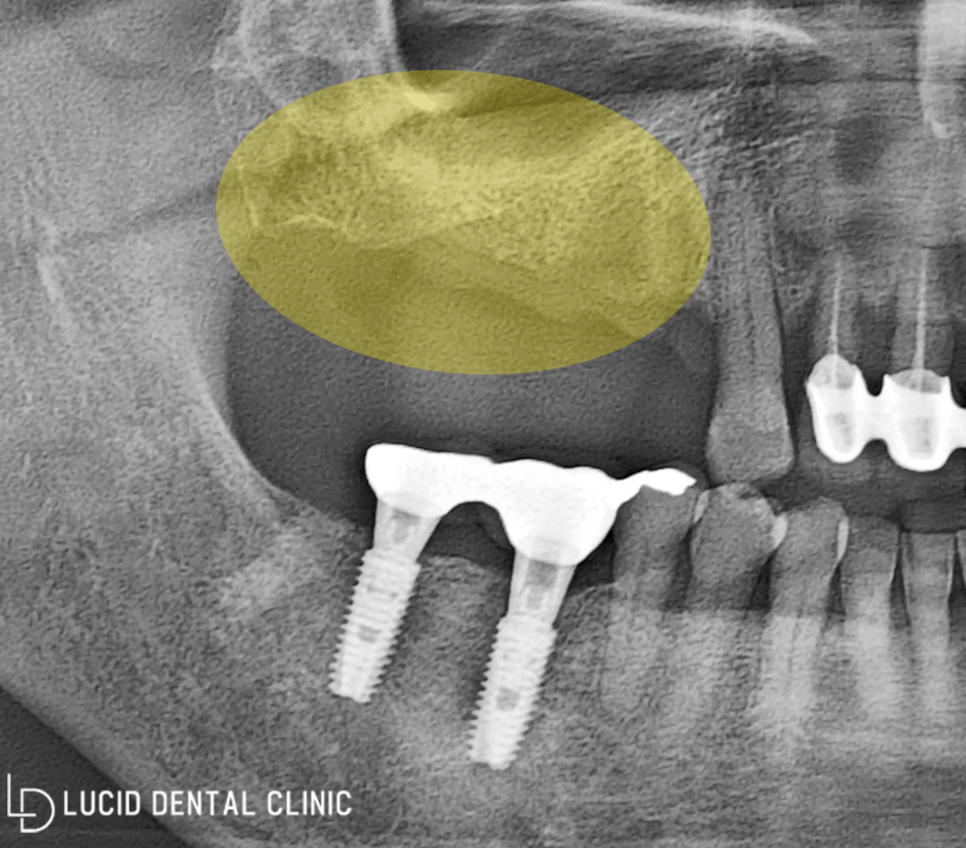

- 초진 당시 파노라마

이 환자께선 이전에 이미

위턱 어금니 발치를 받으셨는데요

일이 너무 바빠 내원할 시간이 없었다며

오랜 기간 방치해 두었다고 말씀하셨습니다.

디지털 파노라마 엑스레이를 통해

환자의 구강을 면밀히 살펴본 결과,

저작 활동을 주로 시행하고 있는

위턱 어금니들이 소실된 모습을

한 눈에 발견할 수 있었습니다.

환자의 경우, 기존 치조골 범위보다

일정 범위 이상 내려간 흡수 증상이 나타났기에

이 상태로 임플란트 식립을 진행하기엔

단단한 픽스처 고정력을 기대하기 어려웠는데요